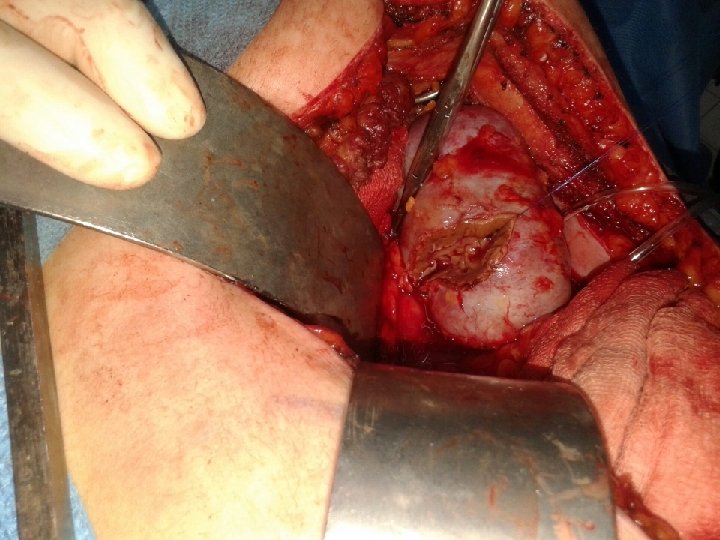

TRAITEMENT 1. Cancer du rein localisé (T 1 -2) Chirurgie du rein ØLe traitement chirurgical est le seul traitement efficace du cancer du rein au stade localisé Néphrectomie totale élargie La NTE est le traitement de référence pour les tumeurs de plus de 7 cm NTE pour cancer a pour but l'ablation en un seul bloc du rein, de la graisse périrénale, de la surrénale, du fascia de Gerota et des gangl Néphrectomie partielle Les chirurgies partielles du rein reposent sur l’exérèse complète de la lésion avec une marge de sécurité de quelques millimètres de parenchyme sain et de graisse périrénale.

Indications de la nephrectomie partielle; Chirurgie conservatrice de nécessité. ØLes patients présentant un cancer sur rein unique, ØUne tumeur bilatérale, ou un rein controlatéral non ou peu fonctionnel. ØLes maladies héréditaires à risque de CCR ØL’indication de néphrectomie partielle peut être relative en cas de maladie pouvant altérer la fonction rénale (lithiases, pyélonéphrite chronique, sténose de l’artère rénale, reflux, diabète, hypertension artérielle). Chirurgie conservatrice de principe. ØLes petites tumeurs sporadiques (moins de 4 cm) exophytiques (limite interne à plus de 1 cm du hile) avec un rein controlatéral normal. Pour certaines équipes entraînées, les tumeurs inférieures à 7 cm (T 1 b) peuvent aussi bénéficier d’une chirurgie partielle.